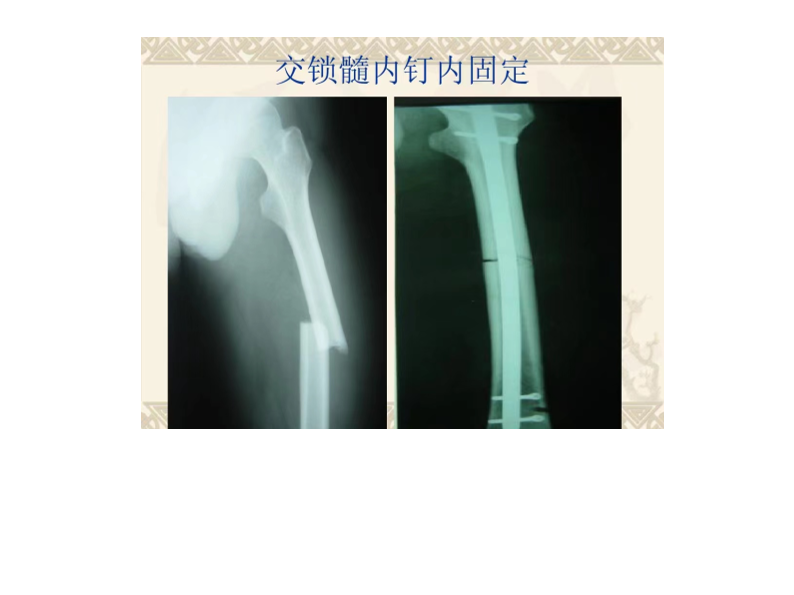

股骨干骨折